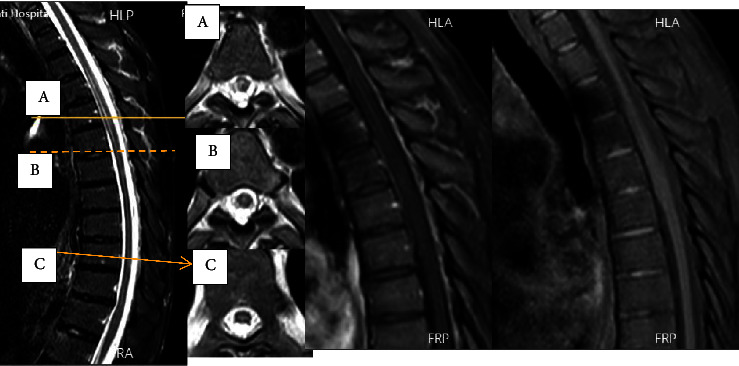

Introduction: Longitudinal extensive transverse myelitis (LETM) has four main causes: inflammatory, malnutrition, vascular, and infectious causes. Among the commonly described viral causes leading to LETM are the Herpesviridae family, HIV, and HTLV-1. Case Presentation. A 43-year-old man presented with asymmetric weakness of the lower limbs (the left side was weaker), urinary retention, and flank pain. The symptoms began five days after shingle eruption and progressed over twelve days. He was diagnosed with longitudinal extensive transvers myelitis extending from T4 to T6, which corresponded to the same dermatome involved in shingles. The PCR result of cerebrospinal fluid was positive for varicella-zoster virus with a viral load of 500 copies/ml. Additionally, the initial HIV enzyme-linked immunosorbent assay (ELISA) test was positive, and his CD4 count was 72 cells/mm3. Other lab results were normal. Based on the appearance of LETM in the thoracic MRI at T4-T6, VZV myelitis was diagnosed, and treatment was initiated with acyclovir (30 mg/kg divided daily for twenty-one days), methylprednisolone (1 g/day for three days), prophylactic antibiotics (trimethoprim/sulfamethoxazole, rifampin, and isoniazid), and antiretroviral therapy (dolutegravir and Truvada). After 2-month follow-up, he was nearly free of symptoms.